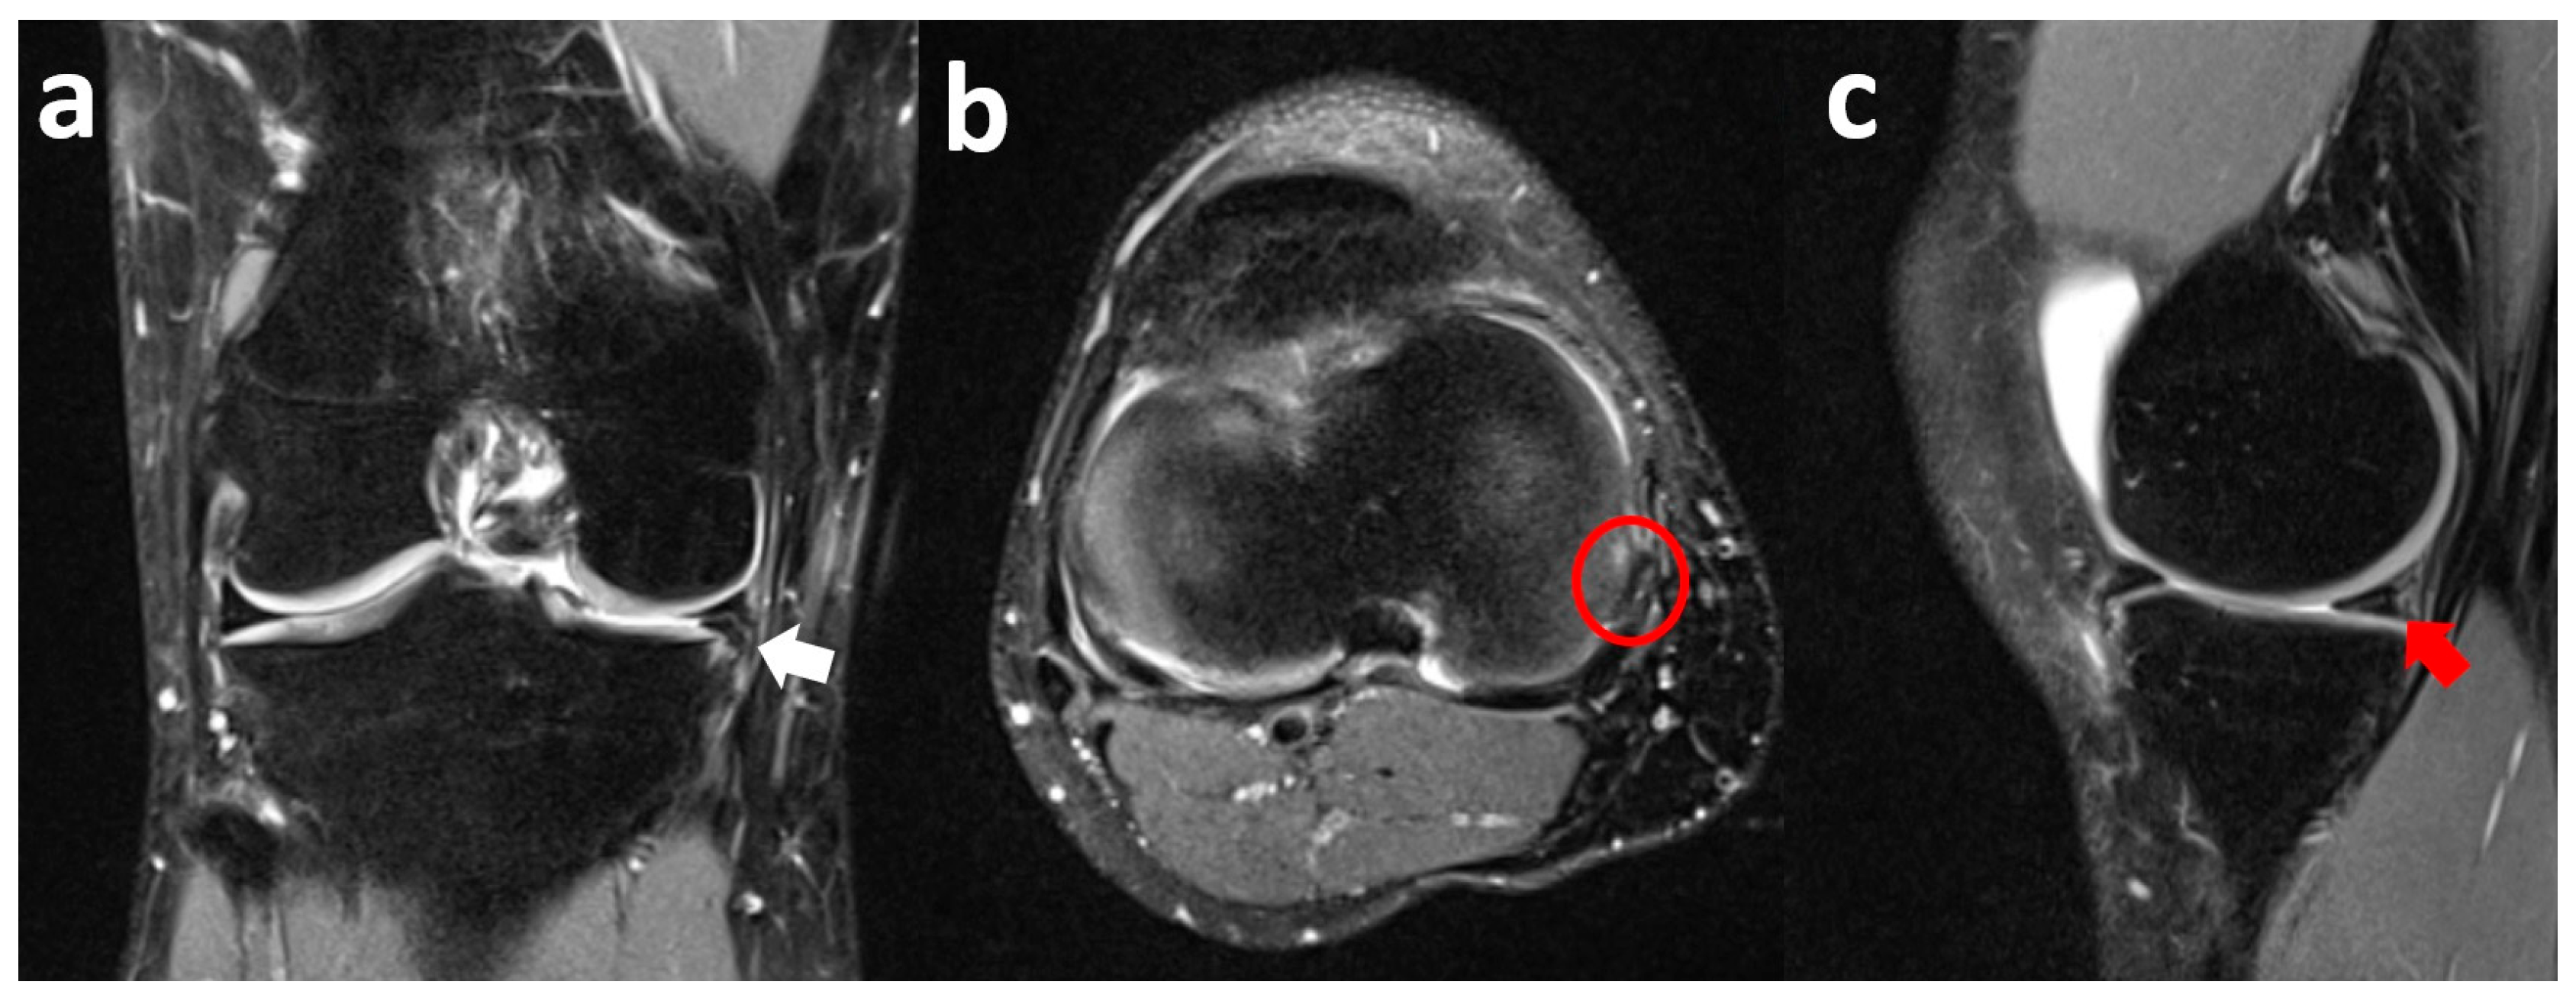

3.3. Medial Meniscus Posterior Root Tear with Extrusion

3.4. Lateral Meniscus Flap in Popliteus Recess

3.5. Lateral Meniscus Flipped in the Lateral Gutter